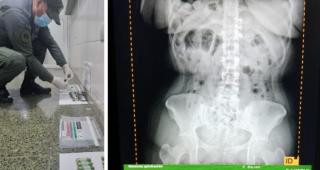

Al momento de la inspección, los funcionarios notaron que tres pasajeras manifestaron molestias abdominales. Ante las altas posibilidades de estar frente a un hecho ilícito, los gendarmes realizaron el traslado de las mujeres involucradas hacia el Hospital de Trancas para realizar las placas radiográficas en donde pudieron observar la presencia de cápsulas.

Teniendo en cuenta la gravedad de la situación debido a que es un riesgo para la salud, trasladaron a las ciudadanas hasta Centro de Salud Zenón Santillán, en la ciudad de San Miguel de Tucumán, a en donde evacuaron un total de 198 cápsulas.

Los envoltorios hallados fueron sometidos a la prueba de campo Narcotest que arrojó resultado positivo para cocaína con un peso total de 2 kilos con 328 gramos.